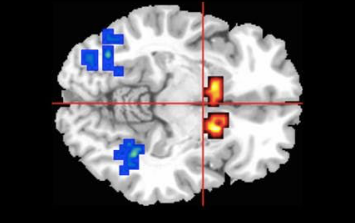

W badaniu zespół brytyjskich naukowców wykazał, że pojedyncza dawka CBD może znormalizować aktywność mózgu związaną z psychozą. Psychozy są powiązane z charakterystycznymi wzorcami aktywacji mózgu, wykrywanymi przez MRI w prążkowiu, przyśrodkowym płatku skroniowym i śródmózgowiu. W podwójnie ślepym badaniu z udziałem 33 osób z wysokim ryzykiem psychozy oraz 19 zdrowych osób, naukowcy odkryli, że osoby zagrożone miały nadmiernie wysoką aktywność w porównaniu do grupy kontrolnej. Jednak wysoka dawka CBD (600 mg) szybko i znacząco zmniejszyła aktywność tych obszarów mózgu do normalnego poziomu.

Naukowcy odkryli, że CBD zmniejsza aktywność jądra ogoniastego (czerwony / żółty), części śródmózgowia związanej z ryzykiem klinicznej psychozy.